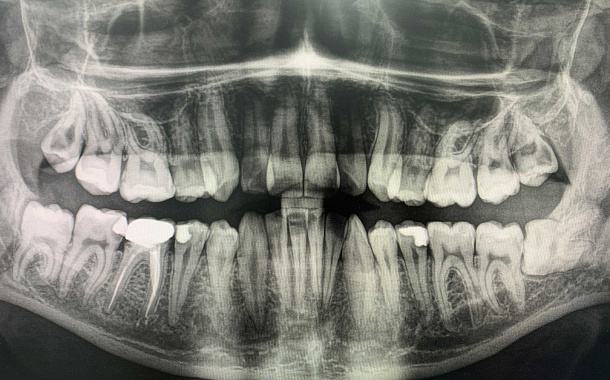

Удаление зуба и кюретаж

Пациент обратился с жалобой на острую боль при накусывании на 37 зуб (нижний зуб слева).

Диагностика показала разрежение костной ткани, обширный воспалительный процесс, который находится в контакте с нижним челюстным каналом.

Принято решение удалить зуб и провести щадящий кюретаж